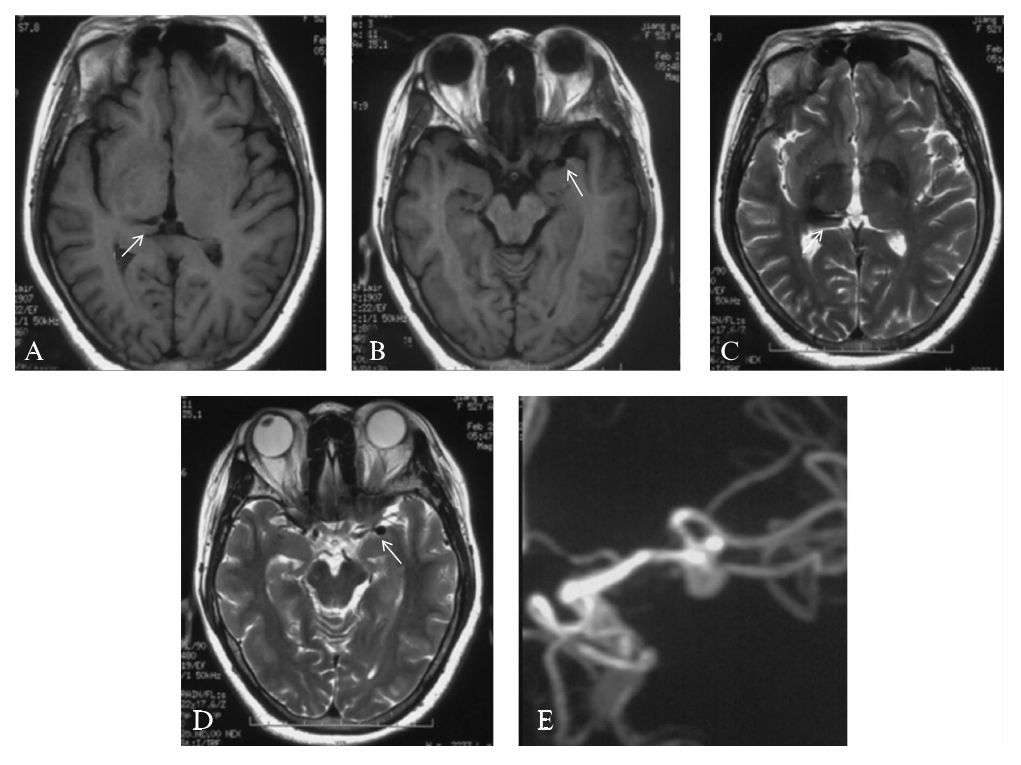

患者,55岁,女性,因“头痛3周”就诊,MRI检查可见右侧丘脑出血后陈旧性软化灶(图10-1A、C),左侧侧裂池内T1WI及T2WI可见局部血管流空影(图10-1B、D),进一步MRA检查证实左侧大脑中动脉动脉瘤(图10-1E)。

患者既往高血压病史7年,最高达180/100 mmHg(1 mmHg=0.133 kPa),平时药物控制不详;3年前有“脑出血”病史。

神经系统查体:神志清楚,言语流利,面纹对称,眼球活动正常,无眼睑下垂等异常,伸舌居中,左侧肢体肌力V-,左侧肢体浅感觉减退。

图10-1 患者入院前MRI及MRA检查

A,C:右侧丘脑出血后T1WI低信号,T2WI高信号的陈旧性软化灶(箭头);

B,D:左侧侧裂池内T1WI及T2WI可见局部血管流空影;

E:头颅MRA证实左侧大脑中动脉动脉瘤

2.影像学检查

MRI、MRA:头颅MRI平扫可见右侧丘脑出血后的T1WI低信号,T2WI高信号的陈旧性软化灶(图10-1A、C),同时左侧侧裂池内T1WI及T2WI可见局部血管流空影(图10一1B、D);MRA证实左侧大脑中动脉动脉瘤,动脉瘤呈分叶状,形态欠规则(图10-1E)。